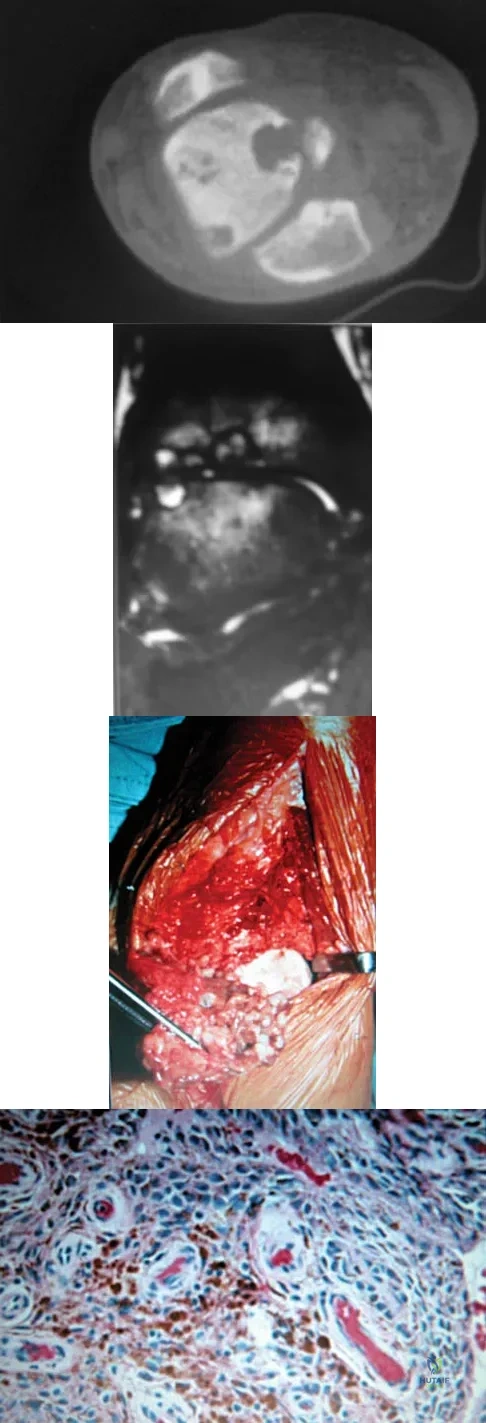

A 14-year-old patient has anterior knee pain. Radiographs, an MRI scan, and biopsy specimens are shown in Figures 6a through 6e. What is the most likely diagnosis?

Although the imaging studies are consistent with a unicameral bone cyst, aneurysmal bone cyst, or giant cell tumor, the histology shows small round blue cells that are typical of Ewing's sarcoma. Although Ewing's sarcoma frequently occurs in the diaphysis, it can occur in the metaphysis.